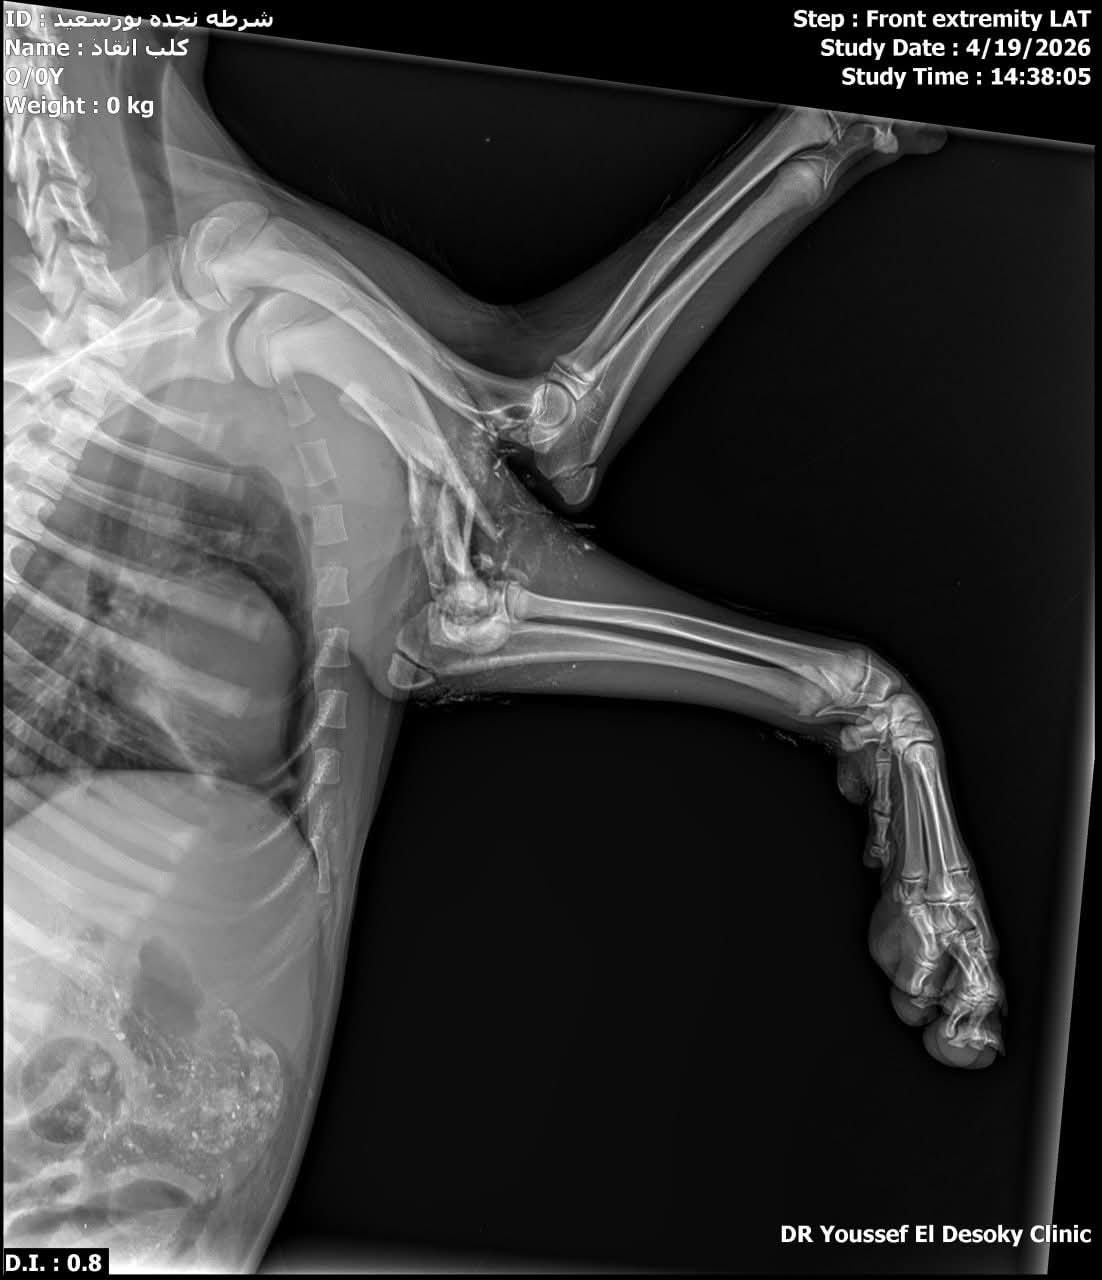

واستجاب النقيب مصطفى صلاح، للموقف، حيث نقل الكلب المصاب بنفسه إلى إحدى العيادات البيطرية، كما جرى التواصل مع الدكتور طارق فرنسيس، مدير مديرية الطب البيطري ببورسعيد، والدكتور محمد عيسى، مدير المستشفى البيطري والمسؤول الطبي عن شلتر بورسعيد، حيث رحبا باستقبال الحالة.

دفعت مديرية الطب البيطري بسيارة مخصصة لنقل الكلب المصاب إلى شلتر بورسعيد، لاستكمال علاجه وتوفير الرعاية اللازمة له، في ظل تفاعل واسع من المواطنين ورواد مواقع التواصل الاجتماعي، الذين أشادوا بسرعة استجابة رجال الشرطة وتعاون الجهات المعنية في إنقاذ الحيوان ورعايته.